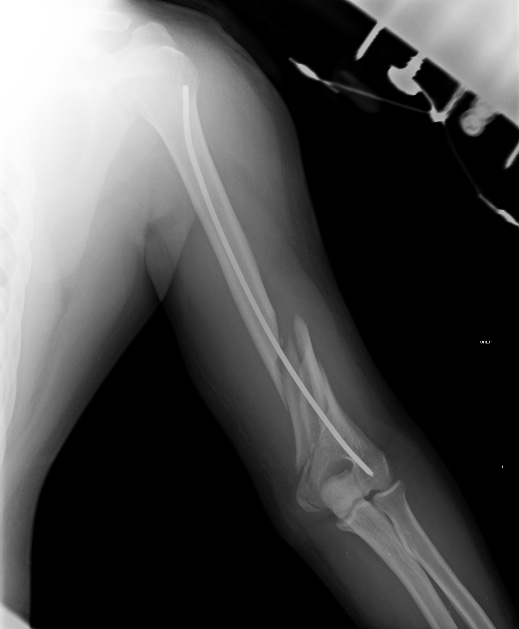

[Ortho] Псевдоартроз н/3 плеча после реЗИМО

Сейчас уже поезд ушел, но если это переделывать, основная мотивация была

бы - выстояние в проксимальном отделе.

Как-то так проксимальный отдел должен выглядеть после аналогичной операции.

Если бы выстояния не было, можно было, например, поверх стержня

наложить простенький аппарат и сдавить. С диастазом не надо было уходить

из операционной.